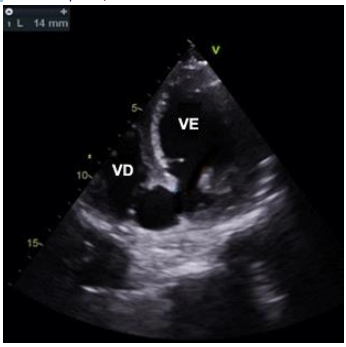

Homem de 60 anos encontra-se internado devido a um infarto agudo do miocárdio com supradesnível do segmento de ST de parede inferior. O paciente foi atendido inicialmente após 10 horas de dor torácica e tratado com terapia trombolítica em uma unidade de pronto atendimento. Em seguida, foi transferido para realização de coronariografia 8 horas depois, que ainda mostrou oclusão proximal da artéria coronária direita. O vaso foi tratado com angioplastia e implante de stent farmacológico, sem intercorrências. Não apresentava lesões residuais em outros vasos. No quarto dia de evolução apresentou rebaixamento súbito do nível de consciência e hipotensão arterial. Ecocardiograma de urgência realizado à beira do leito encontra-se abaixo. VE – ventrículo esquerdo; VD – ventrículo direito.